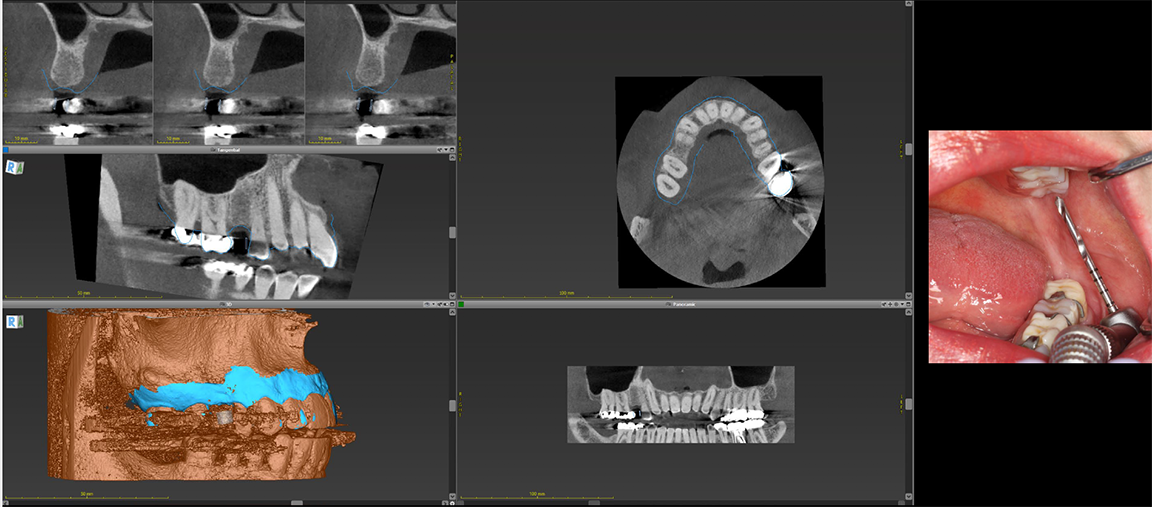

In a more complicated case, often there are more complicated starting points. The patient shown in Figure 8 had bite posture problems, caries, periodontal disease, failing restorations and implants, and a history of head-and-neck cancer. Such a patient may logically fear the unknowns of treatment, but with the treatment planning and rendering capabilities robotics provide, the practitioner could determine exactly what the patient needed, convey the information to the patient, and deliver promised results.

In such a patient, there may be little or no dental topography or teeth with which to work. The CT scan shows only the bony structure, which is what the practitioner is concerned with regarding dental implants, but from a treatment plan standpoint, the practitioner needs to visualize the way through and unwind the complex layers of such a puzzle. Robotics allow the practitioner to employ software on the front end and optimized for the robotic surgical approach in the middle, making the back-end treatment much easier. Scanning templates allow alignment of intraoral scans; the practitioner can add that result with high fidelity back to a CT scan that may otherwise have been unusable (Figure 9). The practitioner also can add other layers, including facial images to start building an improved version of the patient smile. With the data put into the robotic system, the plan is validated with easier to use digital versions that replace older analog treatment planning procedures involving alginate, stone models, articulators, and wax-ups.1-4

With robotics, whether for a simple one-implant procedure or a complicated overdenture or fixed attachable restoration procedure, the steps are the same, starting with aligning data in the robotic software from a treatment plan standpoint. In a case lacking trustworthy teeth, for example, the practitioner can align separate STL files relative to a patient x-ray (Figure 10) and have a blueprint on the screen so that, when designing the implants foundation for yet-to-be-achieved teeth, he or she knows that they will line up.3,4

Fig 8. The patient had bite posture problems, caries, periodontal disease, failing restorations and implants, and a history of head-and-neck cancer.

Figure 8

Fig 9. Scanning templates allow alignment of intraoral scans.

Figure 9

Fig 10. The practitioner can align separate stereolithographic files relative to a patient x-ray.

Figure 10